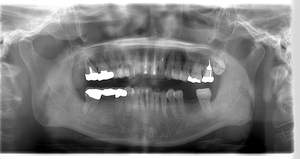

インプラント治療の症例4

レントゲン写真

- Befor

- After

口腔内写真

| 年齢 | 50代・男性 |

| 主訴 | 部位:左下6番7番 主訴:左下奥歯腫れて痛い。 |

| 治療内容 | 左下6番抜歯、左下6番7番骨造成、インプラント埋入 |

| 治療費 | 合計:1,232,000円 ・内訳 診断料:55,000円 サージカルガイド2本:66,000円 GBR:110,000円×2本 埋入料:165,000円×2本 静脈内鎮静麻酔:77,000円 2次OPE:22,000円×2本 仮歯:55,000円×2本 上部構造(フルジルコニア):165,000円×2本 (2023年1月現在) |

| 治療期間 | 約8ヶ月 |

| 治療方針 | 元々支台歯に負荷がかかりやすいとされている延長ブリッジを抜歯し、1本単体でしっかりかめるようにインプラントを2本埋入した。骨吸収も進んでいたため、※GBR法で骨造成を同時に行った。 治療と並行して、全顎的な歯周病治療も行い、今後は歯周病が進行しないよう、こまめにメンテナンスに通っていただく。 |

| 特記事項 | ※1 GBR・・・骨再生誘導法。骨の高さや厚みを人工骨や人工膜などを使用し再生する方法 |

| 担当者所見 | 6番は歯根分割された被せ物が7番の欠損部との延長ブリッジとされており、強い咬合と歯周病も相まって負荷がかかり動揺し、歯として機能しなくなったため、抜歯となった。 |